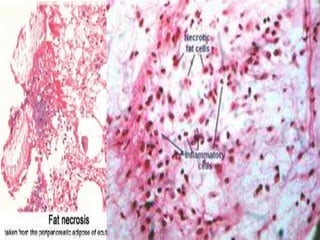

It occurs in two forms:

Enzymatic fat necrosis

Traumatic fat necrosis

 Most commonly seen in acute pancreatitis.

“Refers to the necrosis in adipose tissue, induced

by the action of pancreatic enzymes which are

lead due to trauma to the pancreas”

Morphology

Chalky white opaque spots surrounded by

inflammatory margins are seen

Necrotic area shows acute inflammatory

changes with dissolved fat cells